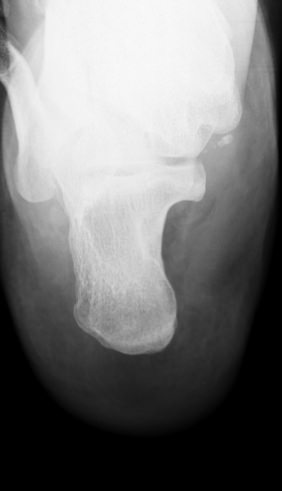

Назад Рентген пяточных костей в боковой проекции

Пяточная кость ― самая крупная среди костей стопы. Нагрузка, приходящаяся на нее, колоссальна. Отсюда и частая травматизация, связанная как со спортом, так и с бытовой и профессиональной деятельностью. Также все патологии, которые развиваются в костной ткани, могут появиться и в пяточной кости. Рентген ― наиболее часто назначаемый вид диагностики при поражении пятки.

На рентгенограмме будут отчетливо видны все структурные изменения, произошедшие с самой пяточной костью и тканями вокруг нее.

Что покажет рентген пяточных костей в боковой проекции

• Целостность кости: переломы, отломки, смещение;

• Состояние костной ткани: разрежение, склерозирование, некроз и другие изменения;

• Конгруэнтность суставных поверхностей и состояние щелей, попавших в область снимка: нормальные, измененные;

• Отечность и инородные тела в мягких тканях пятки;

• Новообразования: опухоли, остеофиты.

Стоит отметить, что остеофиты не являются причиной плантарного фасциита, а вырастают в ответ на хроническое раздражение мягких тканей и свидетельствуют о глубокой стадии заболевания.